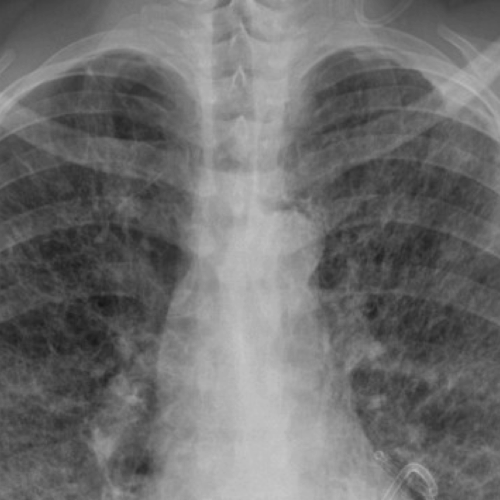

Case 2- AIDS RELATED LYMPHOMA-CT OVERVIEW

NON HODGKIN>>> HODGKIN •ATYPICAL, MORE AGGRESSIVE, POOR PROGNOSIS •EXTRANODAL DISEASE MORE COMMON THAN SEEN IN NORMAL INDIVIDUALS •NOT RELATED TO CD4 COUNT BUT SEEN IN MID /LATE PHASE